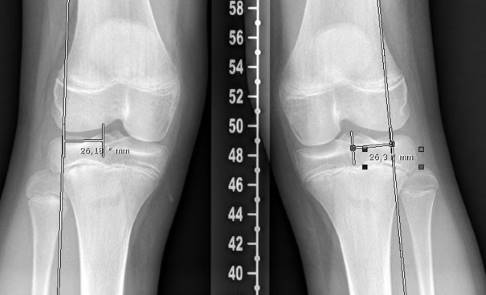

In einer Röntgenaufnahme des gesamten Beines kann der Arzt das Ausmaß der Abweichung von der Mitte des Kniegelenks genau bestimmen. Der Wert wird als MAD (mechanische Achsdeviation) in Millimetern angegeben. Zusätzlich wird der exakte Winkel der Achsabweichung ausgemessen.

Um die mechanische Achsdeviation (MAD), also das genaue Ausmaß der Abweichung von der Mitte des Kniegelenks abzuschätzen, ermittelt der Kniespezialist die Mikulicz-Linie. Diese bestimmt er anhand der Röntgen-Ganzbeinaufnahme. Sie führt vom Zentrum des Hüftkopfes bis zur Mitte des oberen Sprunggelenks. Verläuft die Mikulicz-Linie nicht mittig durch das Kniegelenk, sondern durch die Innenseite, handelt es sich um eine Varusfehlstellung (O-Bein). Verläuft sie durch die Außenseite des Kniegelenks, liegt eine Valgusfehlstellung (X-Bein) vor. Zusätzlich wird der exakte Winkel der Achsabweichung ausgemessen.

Zur Einschätzung der Beinachsenfehlstellung wird die Ganzbein-Röntgenaufnahme des Kniegelenks von vorne in 4 Quadranten eingeteilt. Verläuft die Mikulicz-Linie und somit die mechanische Beinachse innerhalb der beiden mittleren Quadranten, liegt eine normale bzw. geringgradig abweichende Beinachse vor, die nicht operativ korrigiert werden muss. Verläuft die Beinachse außerhalb der inneren Quadranten, liegt eine pathologische (krankhafte) Beinachse vor.